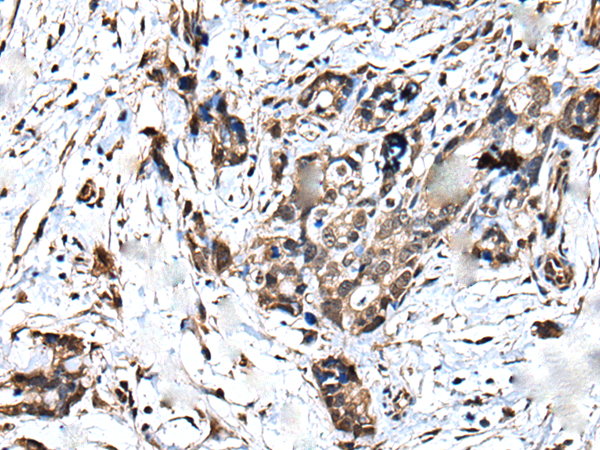

IHC positive control: |

Human thyroid cancer and human gastric cancer |